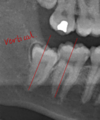

How would you assess a radiograph

- interruption of white lines/lamina dura of the canal - darkening of the root where crossed by the canal - diversion/deflection of the IAN canal - deflection of root - narrowing of the IAN canal - narrowing of the root - dark and bifid root - juxta apical area

What radiograph signs are associated with a significantly increased risk of nerve injury during 3M surgery

1. diversion of the inferior dental canal 2. darkening of the root where crossed by the canal 3. interuption of the white lines of the canal

28

Describe the IAN canal

Diversion/deflection of the inferior dental canal

29

Describe the IAN canal relationship

darkening of the root where crossed by the canal

30

describe the relationship to the IAN canal

interruptioni of the white lines/lamina dura of the canal

31

deflection of root

32

Assess radiographically

narrowing of the inferiror dental canal

33

narrowing of the root

34

dark and bifid root (splits/divides over canal)

35

juxta apical area